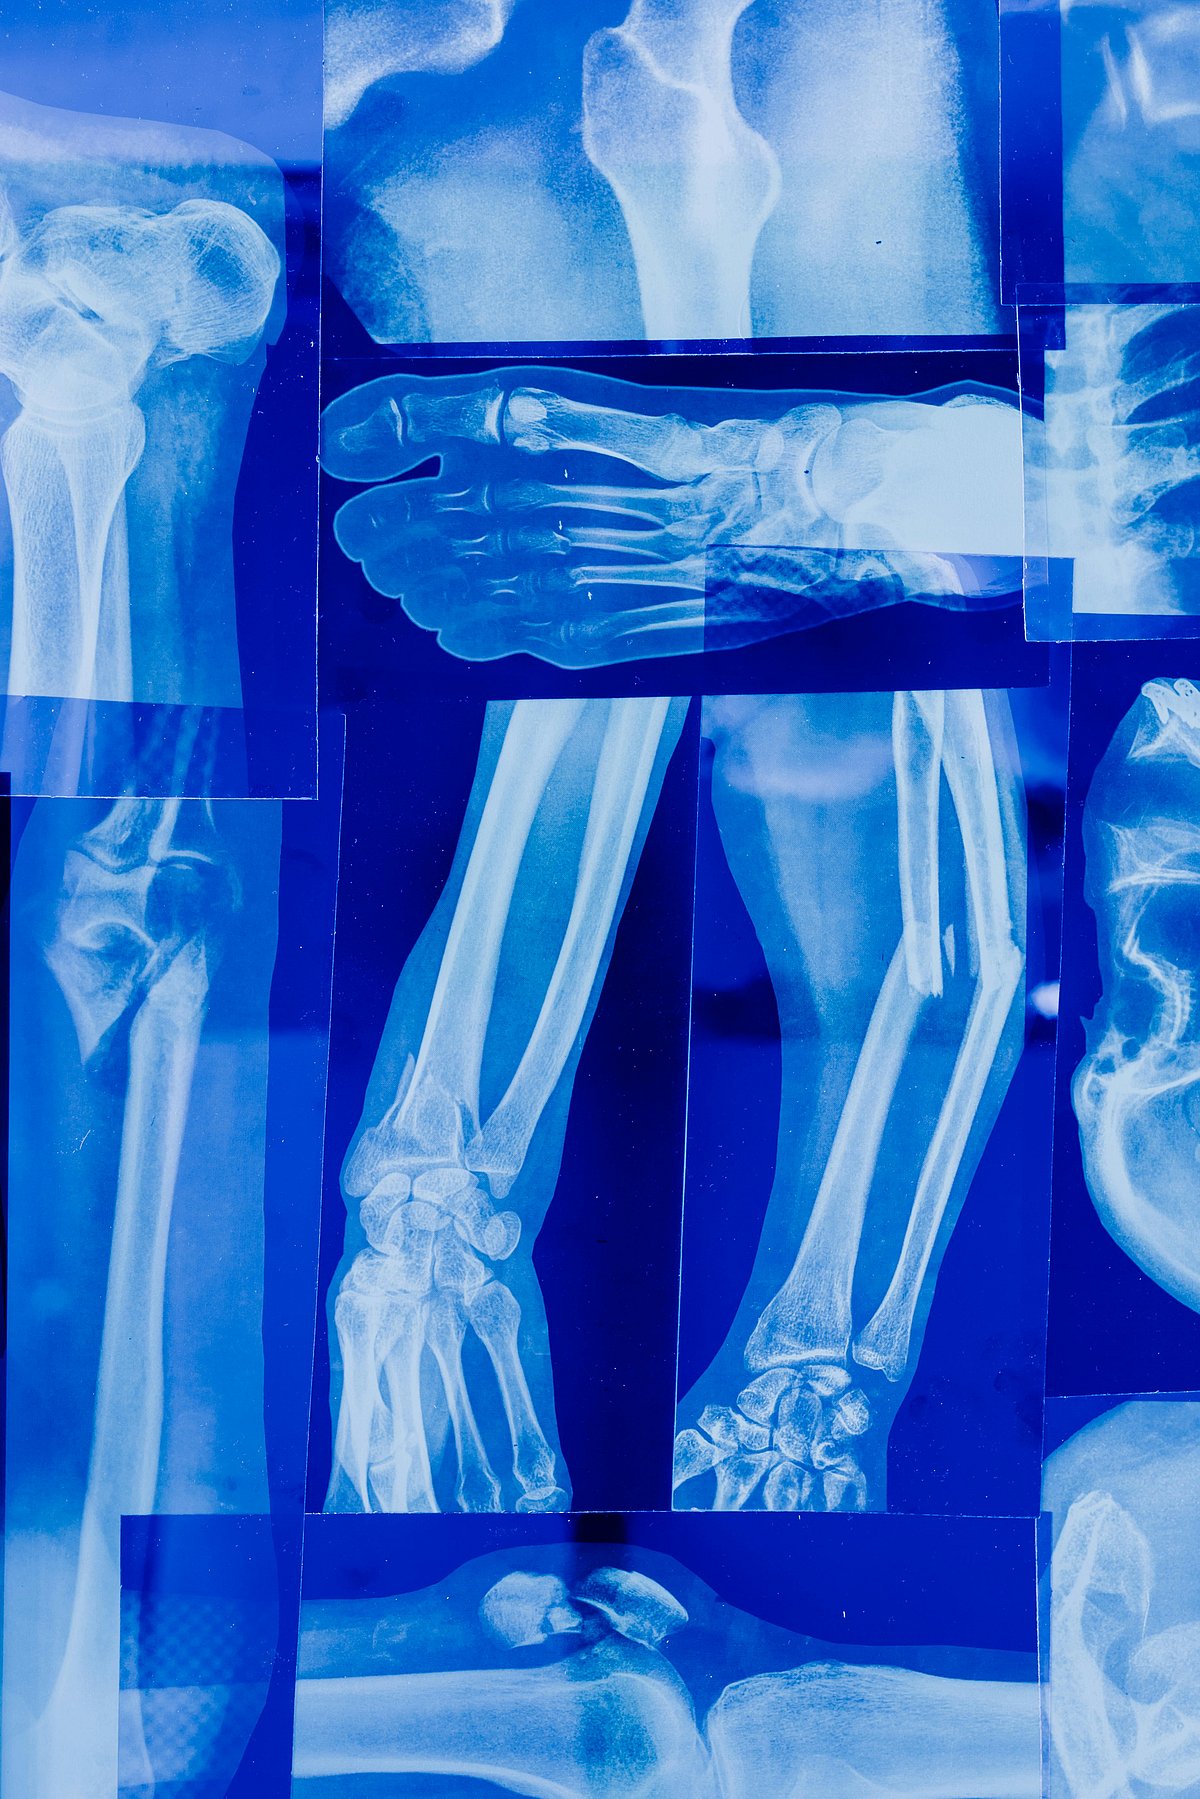

বিলম্বে হাড় জোড়া লাগা একটি বিশেষ সমস্যা। প্রতিদিন অসংখ্য রোগীর হাড় ভাঙে; সঠিক চিকিৎসা পেলে কিছুদিনের মধ্যে তা জোড়াও লাগে। তবে হাড়ভাঙা-পরবর্তী সময়ে বিভিন্ন জটিল সমস্যা হতে পারে।

হাড় ভাঙার তীব্রতা, স্থান ও রোগীর শারীরিক অবস্থার ওপর এটি জোড়া লাগার সাফল্য অনেকাংশে নির্ভর করে। যদি চার থেকে ছয় মাসের মধ্যেও জোড়া না লাগে, তবে তাকে ডিলেইড ইউনিয়ন বা বিলম্বিত জোড়া বলা যায়। আর ৯ থেকে ১২ মাস পেরিয়ে যাওয়ার পরও জোড়া না লাগলে, তাকে নন–ইউনিয়ন বা জোড়া না লাগার সমস্যা হিসেবে আখ্যায়িত করা যায়।